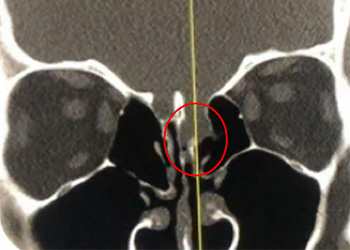

Endovascular:

Hydrocephalus and Brainstem Tumor

Author: Jonathan L. Brisman M.D., F.A.C.S., Read More!